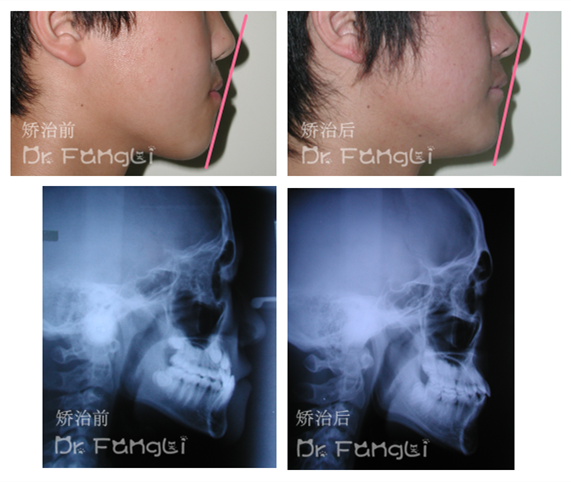

而对于严重的骨性反颌,如果患者已经是成年人,但想达到最佳的治疗效果,手术是最后的希望。地包天的形成不是因为下颌骨发育过于前伸,上颌骨相对不足吗?那把下颌骨截掉一段,上颌骨往前拉一拉不就可以了吗?

是的,临床上手术治疗骨性反颌就是这么做的。手术前后联合正畸,颌骨畸形牙齿畸形一并解决,你便可以成为你理想中的模样,但是相较于漫长温柔的牙齿矫正技术,手术治疗的策略可以说既有创伤又增加了风险。